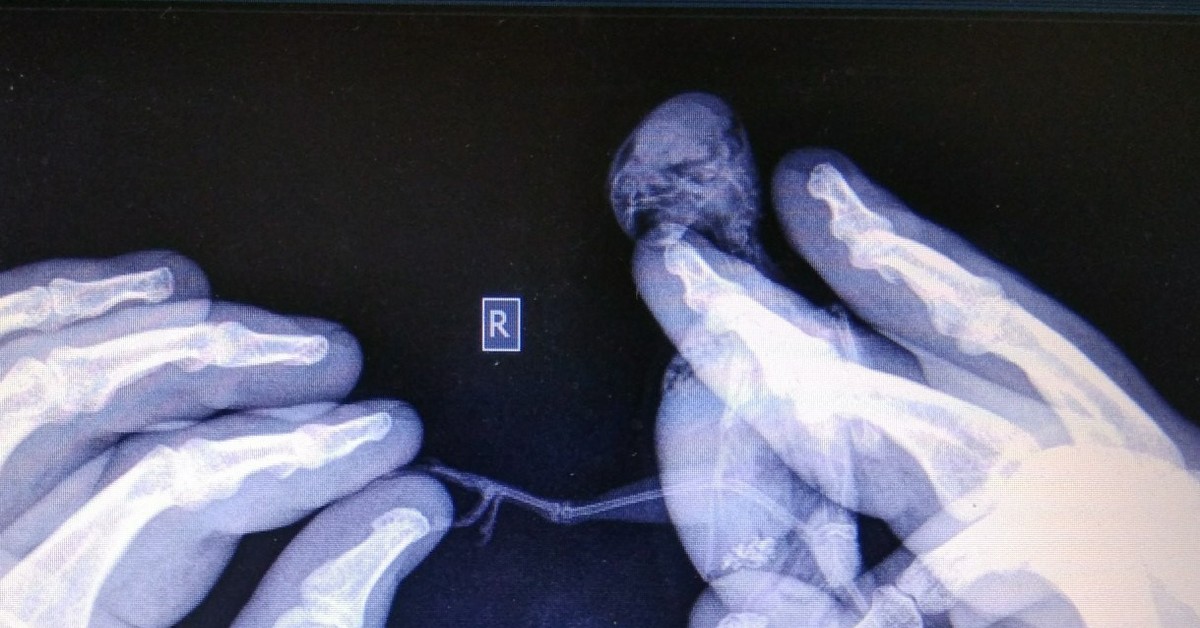

Рентген попугаю

Рентген попугаю 117 фото